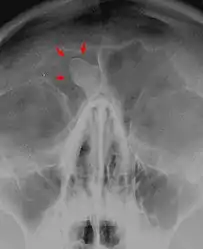

| CT scan showing an osteoma growing on inside of skull bone | |

Medical imaging such as X-ray, CT scan and MRI show dense, clearly defined, round white tumors attached to bone.[1] They may be diagnosed when having medical imaging for another reason.[3] Osteomas of the paranasal sinuses and skull base can be diagnosed using CT-scan without intravenous contrast, allowing its size and relation to nearby important structures to be assessed.[3] A biopsy is not usually required.[3]

CT-scan skull: Osteoma of the frontal sinus